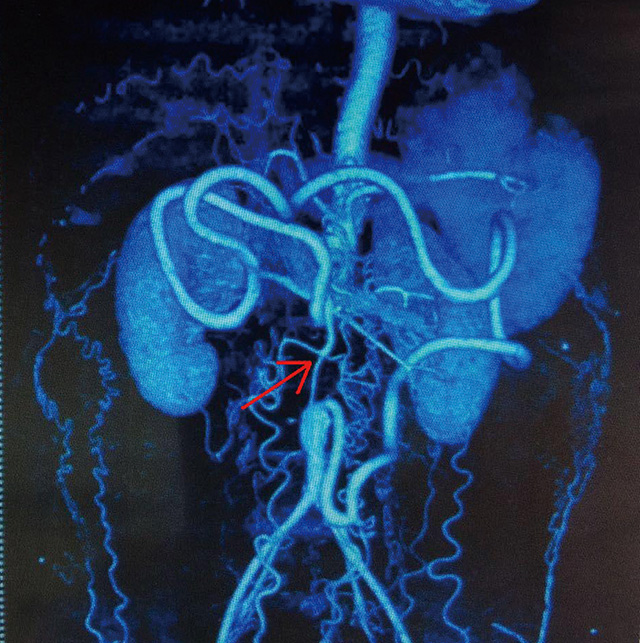

入院后,普外科首席專家李森教授和主管醫(yī)生為孫先生做了詳細的查體,發(fā)現(xiàn)病人雙下肢皮溫較低,右足踇趾、中趾缺如,中趾處創(chuàng)面觸痛明顯,雙足血供差,可見多處潰瘍愈合疤痕,雙側(cè)股動脈、腘動脈、脛后動脈、足背動脈搏動未觸及。動脈強化造影示腹主動脈及雙側(cè)髂總動脈完全閉塞,僅有少量交通支與遠側(cè)髂外動脈相通。明確診斷為腹主動脈硬化閉塞癥。根據(jù)各項相關(guān)檢查證實,病情是在腹主動脈硬化閉塞癥導(dǎo)致的嚴重肢體缺血癥狀,必須行血管轉(zhuǎn)流術(shù),才能獲得較好的治療效果,否則只能截肢。

(病人術(shù)前的相關(guān)影像學(xué)檢查資料:紅色箭頭處顯示主動脈腎下段充盈缺損,周圍側(cè)支循環(huán)建立)